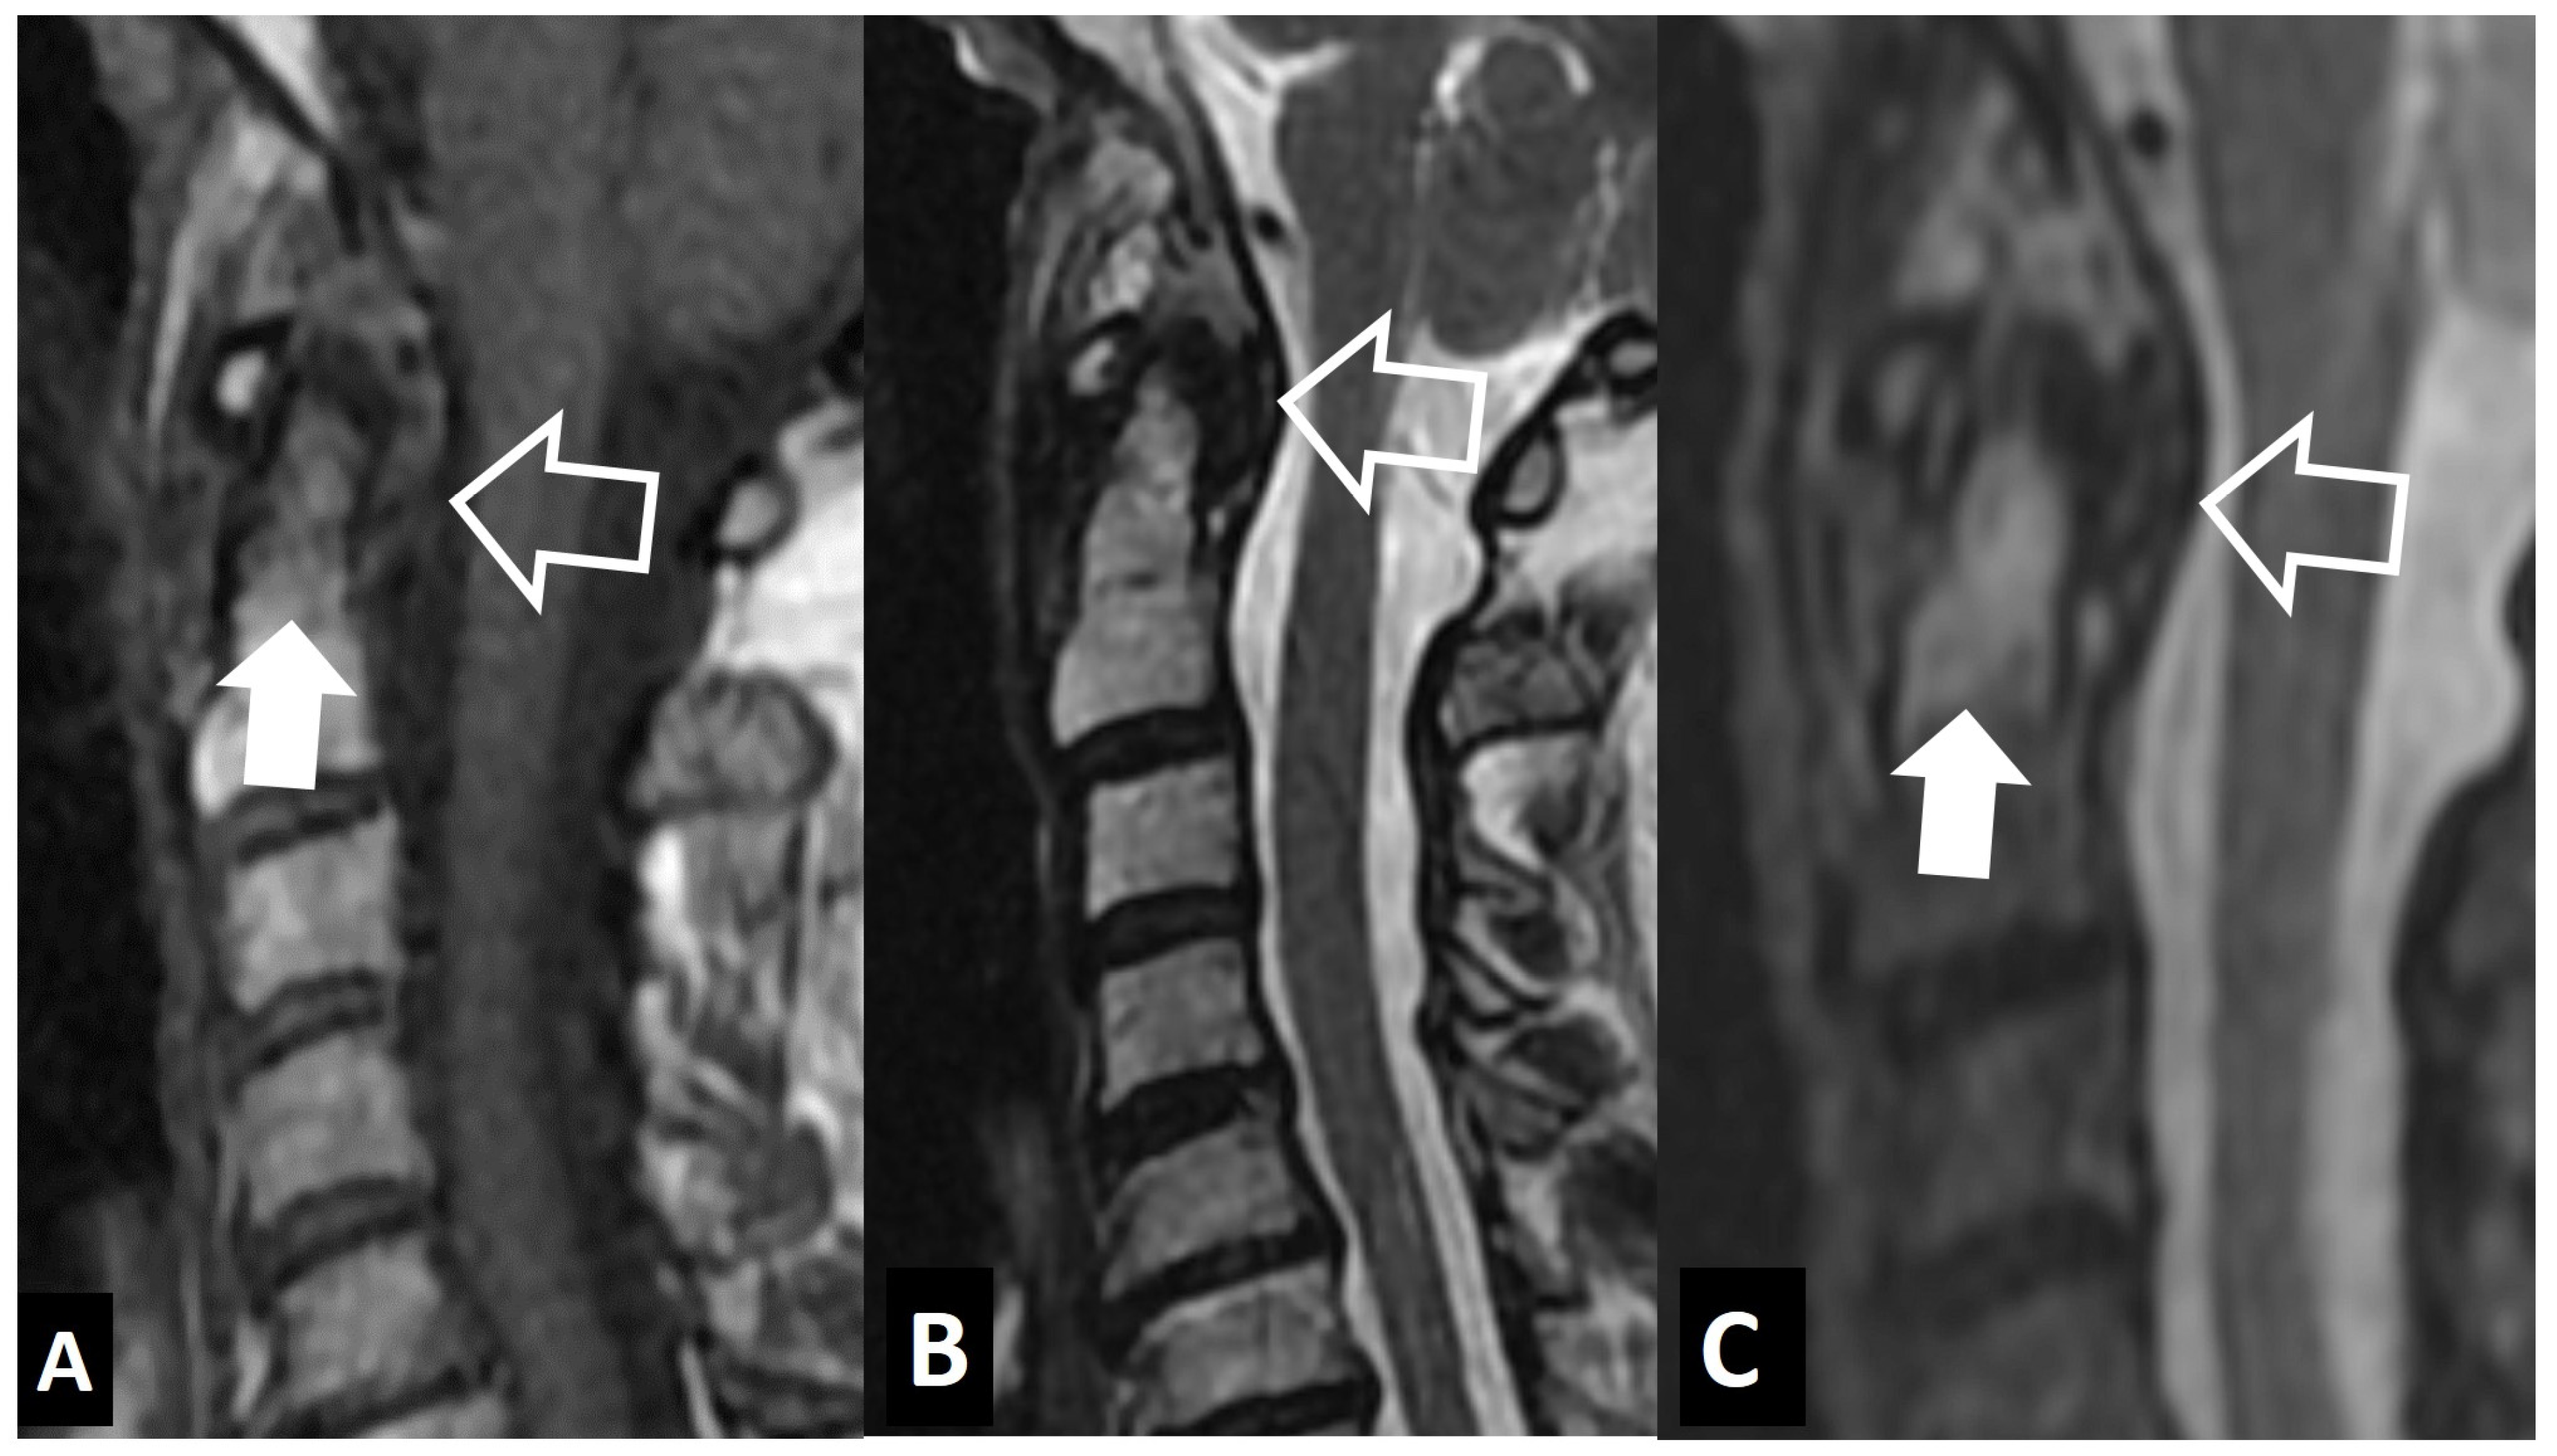

2.1.3. SAPHO Syndrome

- Kim, S.-K.; Shin, K.; Song, Y.; Lee, S.; Kim, T.-H. Andersson lesions of whole spine magnetic resonance imaging compared with plain radiography in ankylosing spondylitis. Rheumatol. Int. 2016, 36, 1663–1670. [Google Scholar] [CrossRef] [PubMed]

- Madsen, K.B.; Jurik, A.G. MRI grading method for active and chronic spinal changes in spondyloarthritis. Clin. Radiol. 2010, 65, 6–14. [Google Scholar] [CrossRef]

- Park, Y.-S.; Kim, J.-H.; Ryu, J.-A.; Kim, T.-H. The Andersson lesion in ankylosing spondylitis: Distinguishing between the inflammatory and traumatic subtypes. J. Bone Jt. Surg. Br. 2011, 93, 961–966. [Google Scholar] [CrossRef]